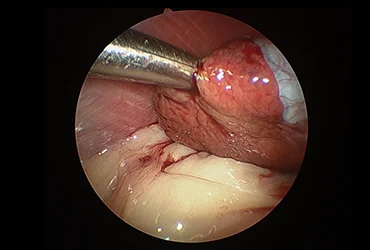

(진단/협진 사례: 간염 환자의 복강경 생검, 간종양 환자의 경우 외과 협진을 통한 복강경 종양 제거 계획 수립)

치료 과정에서 외과와의 긴밀한 협력을 통해 담낭 절제, 종양 제거, 장관 이물 제거 등 필요한 수술적 처치를 원활하게 연계하며,